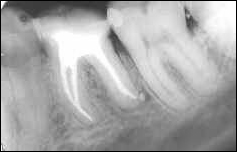

La première image montre une dent saine sans atteinte carieuse Relatif à la carie; Qui se carie.. La carie débute au niveau d’un sillon profond et, après avoir franchi l’émail, elle évolue au sein de la dentine progressant en direction de la pulpe. Non traitée, elle atteint et provoque une inflammation qui tend vers des douleurs de plus en plus violentes. On dépulpe la dent pour soulager ces douleurs : c’est la dévitalisation.

On ouvre la dent pour enlever tous les tissus infectés ou atteint de lésions inflammatoires ainsi que les bactéries et tous les débris organiques se trouvant dans le canal. Une fois désinfecté et élargi, le canal est obturé Boucher une ouverture. par une pâte qui va durcir et protéger la dent de toute infiltration bactérienne. Les premiers jours, une sensibilité se fait sentir mais s’estompe petit à petit.

AVANT

APRES

La pâte va jusqu’au bout des canaux.